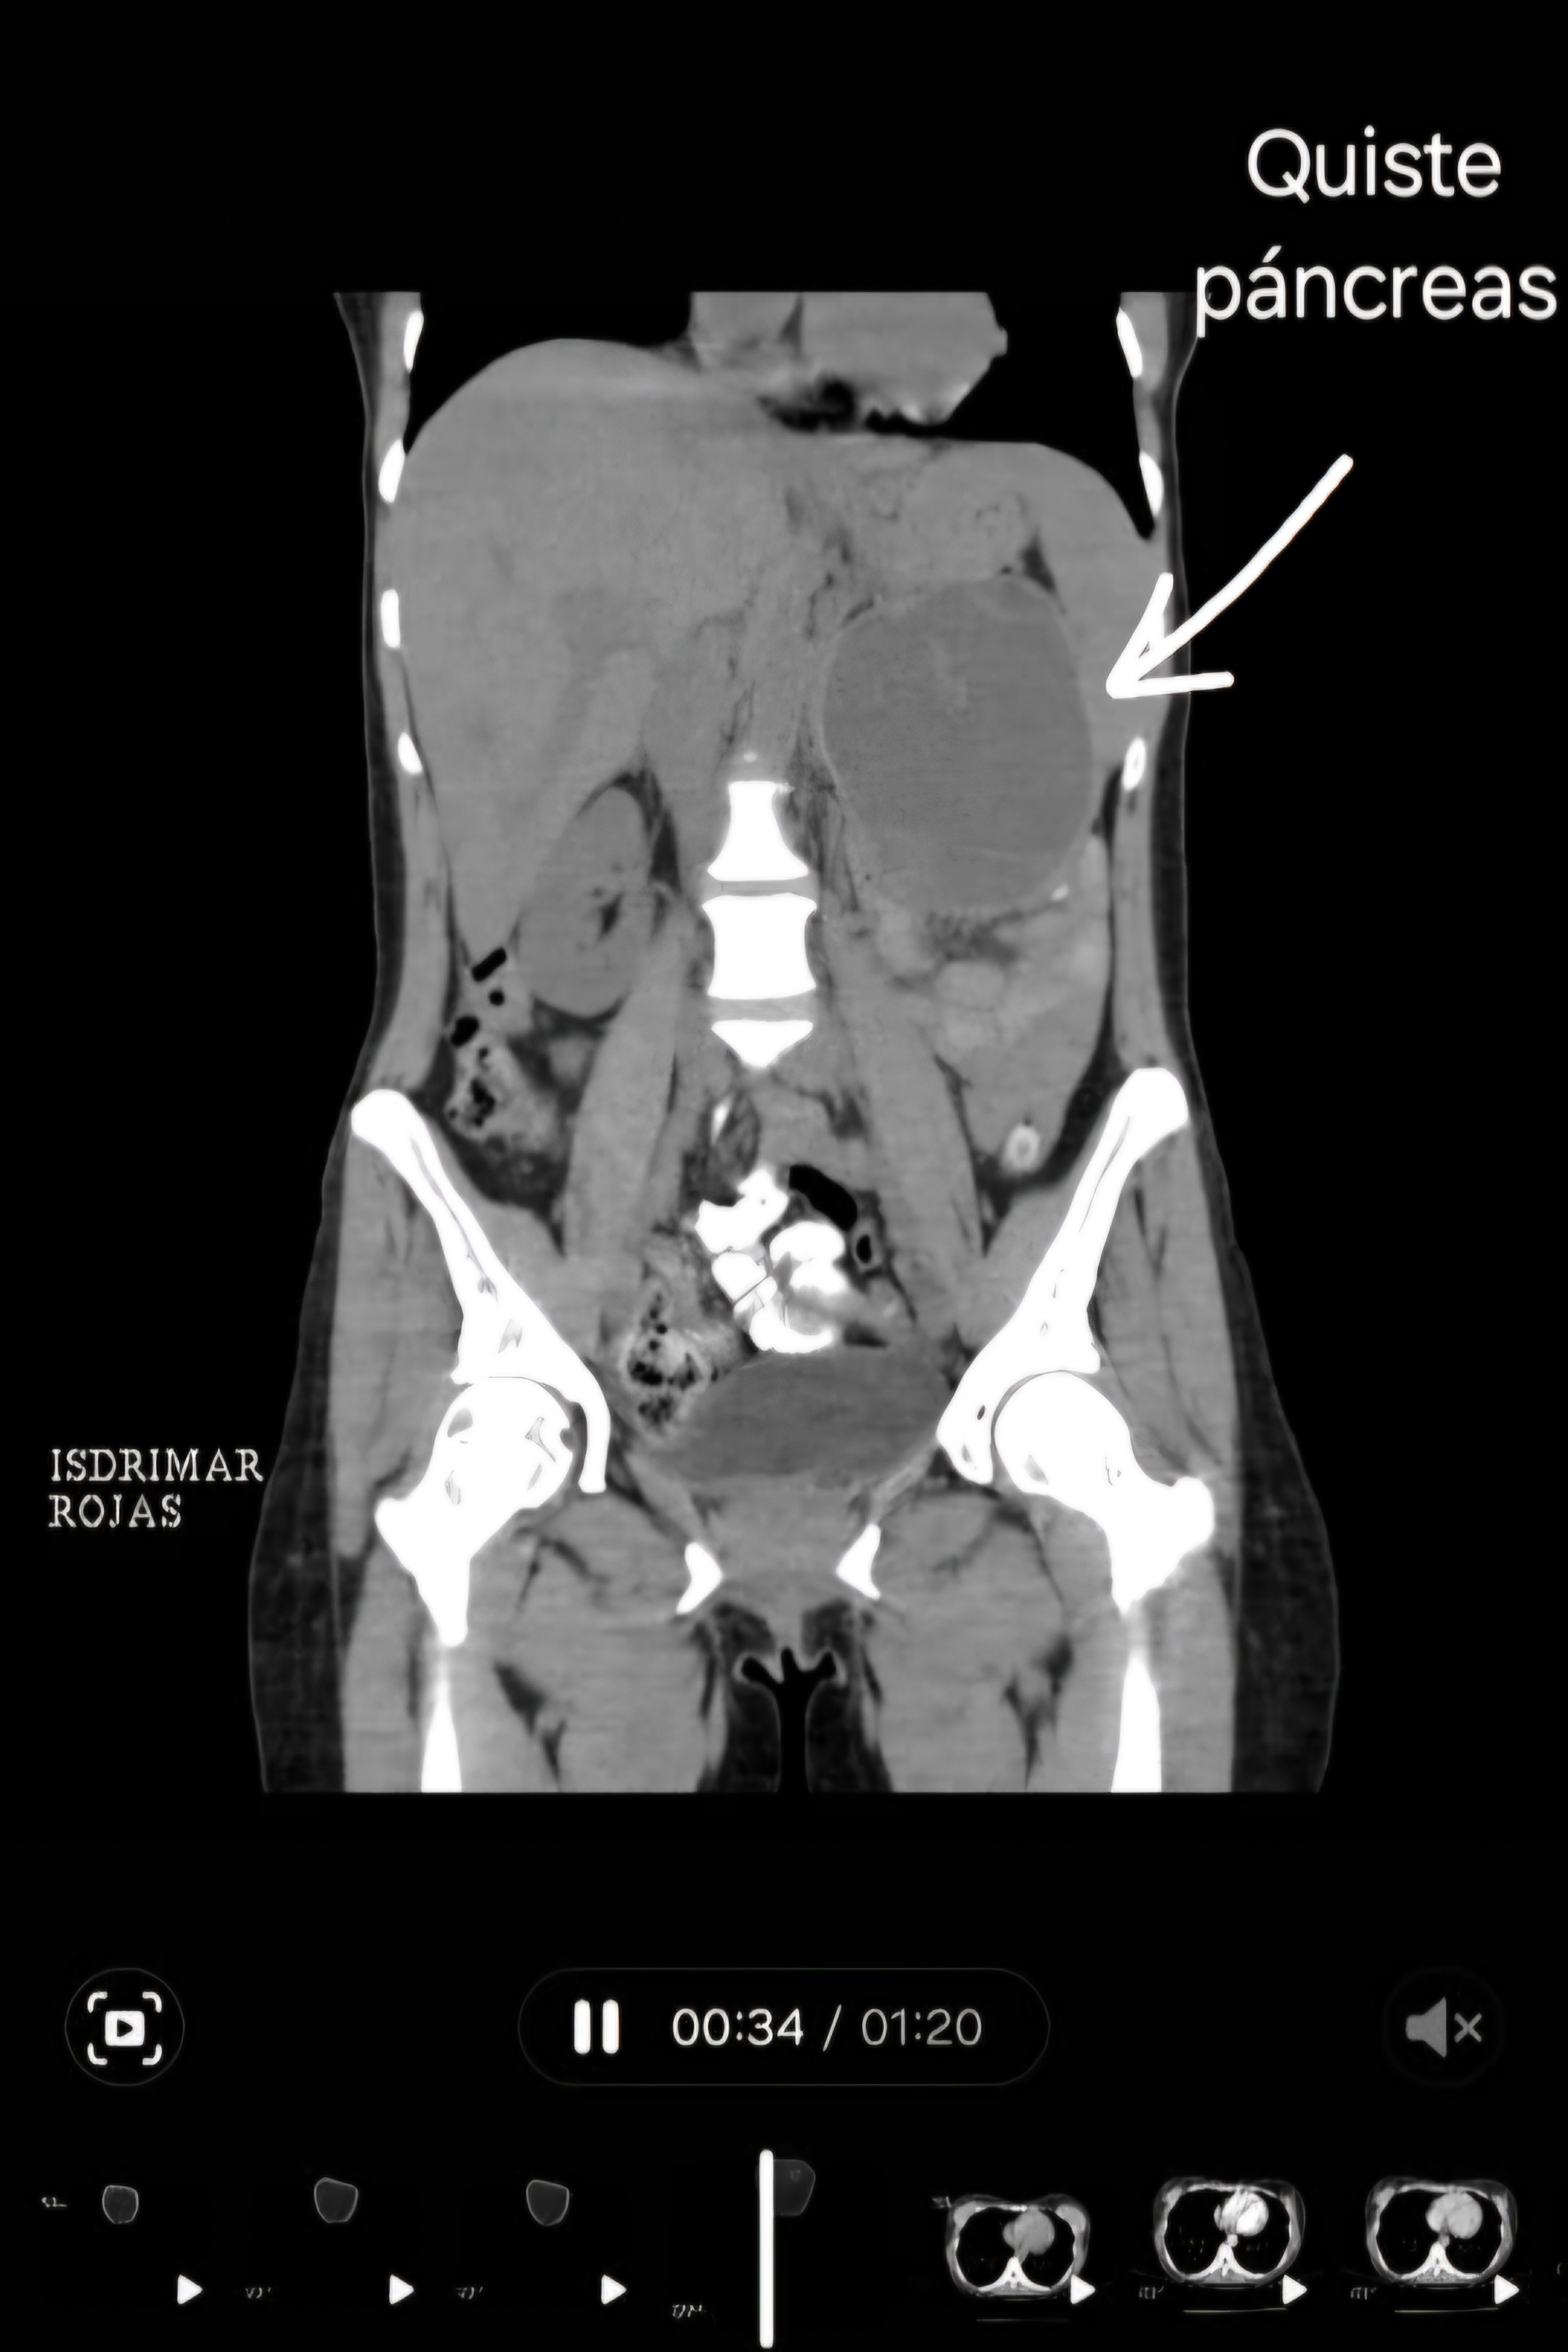

Hoy quiero compartirles una actualización muy importante sobre la situación de mi hermana. Como muchos de ustedes saben, mi hermana isde tiene 39 años es madre de una niña hermosa de 13 añitos y en las últimas semanas ha estado luchando contra un diagnóstico bastante delicado inicialmente de quiste en cola de pancreas que ha resultado en un cáncer de páncreas avanzado, y la realidad es que necesitamos su ayuda hoy más que nunca.